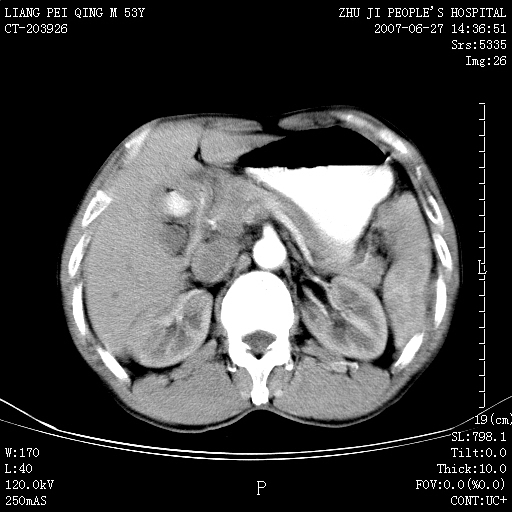

以下是引用余辉在2007-6-27 18:46:00的发言:[br]病灶多发,内可见大片状低密度区,病灶病灶等密度区轻度强化,动脉期后期病灶低密度区与高密度区对度增加,考虑1淋巴瘤2转移瘤3血管内皮细胞瘤(不知有否静脉期及延迟期扫描)

以下是引用zzzzhhhhaaaannnn在2007-6-27 20:44:00的发言:[br]脾脏 肋骨转移可能性大,下腔静脉内有癌栓

以下是引用狙击手在2007-6-28 10:35:00的发言:[br]1:定位:来源于脾脏。2:强化:强化,但不均匀。3:下腔静脉癌栓?下腔静脉充填不均匀与增强时间有关,延时即可明确。4:肋骨破坏?看起来并不确切。综上考虑几个最常见诊断:1;淋巴管瘤;2;血管内皮肉瘤(高度恶性,早期即可转移,常见肝,肺,骨)3;转移瘤(无特征性,只有肝或其它腹腔脏器有类似病变时,才可提示之)